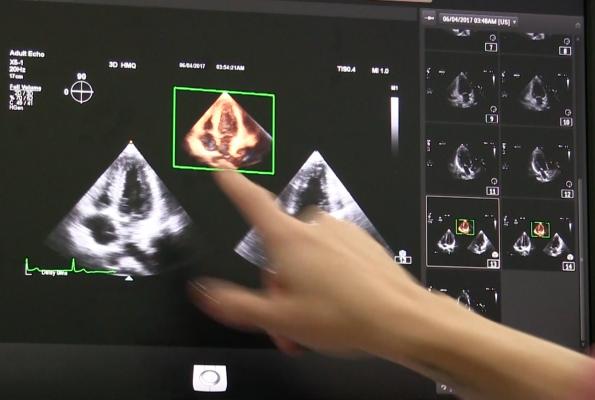

Researchers explored the bilateral carotid and femoral arteries of 3,860 middle aged participants without prior cardiovascular disease who were employees of the Banco de Santander in Madrid, Spain. This is an ongoing observational prospective cohort study where participants are being followed up for 10 years. The 3DVUS examinations were performed using a new Phillips iU22 ultrasound system equipped with a VL13-5 3D volume–linear array transducer. This equipment will be available in the near future for routine patient care.

The clinical application of 3DVUS techniques is still at the research and development stage, but there are now a number of clinically promising areas including the measurement of plaque. Direct quantification of atherosclerotic plaque volume by 3DVUS is more reproducible than two-dimensional techniques.

“3DVUS is a feasible, reproducible, and novel imaging technique for quantifying early carotid and femoral atherosclerotic burden in large populations,” said the study’s lead author, Valentin Fuster, M.D., Ph.D., director of Mount Sinai Heart and physician-in-chief of The Mount Sinai Hospital. “This novel method is valid for imaging superficial peripheral atherosclerosis burden from early to advanced stages of disease and can be applied to identification of individuals at risk, targeting or monitoring treatment. Further studies are needed, however, to assess the cost utility of this method compared with others when used in large-scale practice settings and population-based epidemiological studies.”